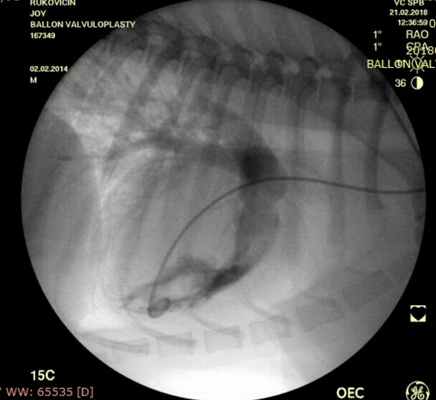

Проведено: баллонная вальвулопластика клапана легочной артерии (Тип А). Баллон Cordis maxi 40х20 мм. Инфляция до 5 атм. 10 попыток.

ЭхоКГ (после операции): ГД (градиент давления) на ЛА (легочной артерии) - 39 мм.рт.ст. РКЛА (регургитация клапана легочной артерии) – ср. - 16 мм рт.ст. Геометрия сердца не нарушена. Выраженное снижение градиента давления после баллонной дилатации КЛА (клапана легочной артерии) на 55%.